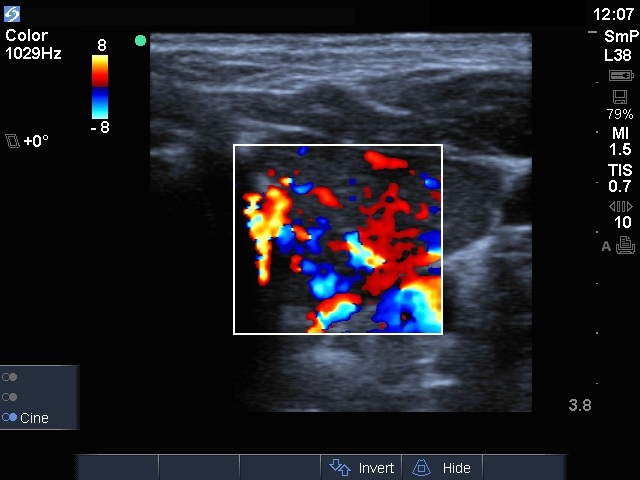

Left lobe, color Doppler mode

Compare the two series of pictures. The clinical presentation was almost the same in these two cases. Patients were referred for an evaluation of clinical and biochemical hyperthyroidism. The FT4 level was more than double of the upper normal limit in both cases. Patients had neither pain or tenderness, nor subfebrility or fever, nor eye complaints. The only difference was the ultrasonographic pattern. The patient with Graves' disease had diffuse hypoechogenicity and substantially increased thyroid blood flow. However, the patient with de Quervain's thyroiditis had a patchy hypoechogenic pattern and decreased blood flow.